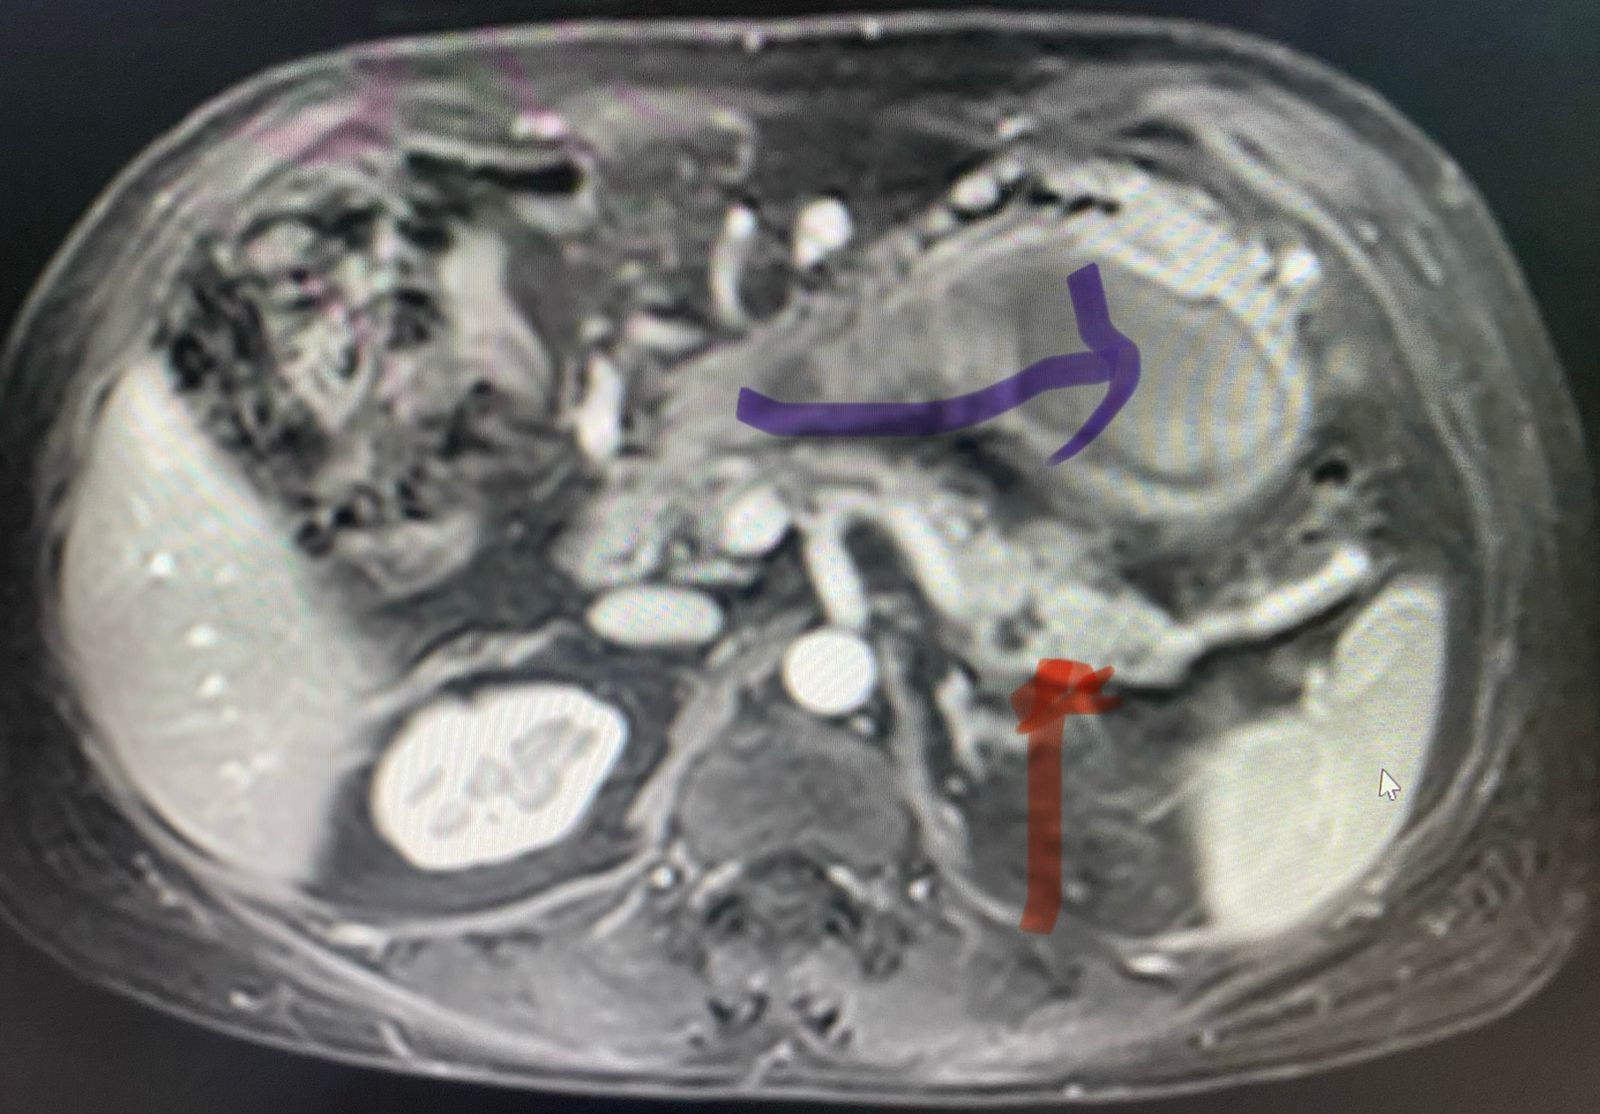

A 54 year old gentleman presented with acute abdominal pain since 5 days accompanied by vomiting. His investigations revealed a suspicious pseudo cyst of pancreas on ultrasonography and CT scan of the abdomen. A careful re look of the CT scan followed by an MRCP suggested a leak from pancreatic duct at the junction of body and tail of the pancreas. This had led to formation of a pseudo cyst (image - pseudo cyst : blue arrow, duct leak area - red arrow).